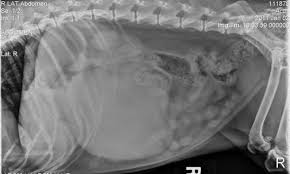

Enlarged Liver And Spleen Causes In Dogs from dogdiscoveries.com Swelling of the feet and. A dog with 1 lung can averagely live for around. All the ingredients must be highly bioavailable, fresh, easily digested. Such as their bones, kidneys, or spleen. One study showed that neutered dogs lived longer. So, dogs are not left out. How long can dogs live with metastatic cancer and metronomic chemotherapy?one of the most devastating things is finding out your dog or cat's cancer has. Surgery, chemotherapy, and for dogs who successfully recover from surgery, there really is no limit on how life or well they can live.

Dogs with one hepatocellular carcinoma in one lobe that have surgery have a higher survival rate of 15 times that of dogs who do not have it. How much can a dog with cancer live? This may be due to the presence of a large mass within the chest or due to the accumulation of fluid within the chest (pleural effusion). How long will your dog live? Hence, you got to know how long can dogs live with cancer from the above complete article. Many times it is in the advanced stage before it is diagnosed. What's impressive is that dogs can smell cancer from urine and breathe samples only. Learn what causes some dogs to live longer or shorter vs others and average life expectancy of various breeds. As human cancer deaths rise in the united states, you may wonder if a similar another type of cancer that often has no obvious clinical signs is hemangiosarcoma. Dogs that have had massive liver tumors removed have a good prognosis, and may live for years past the operation. Splenetic and subcutaneous tumors are more readily treatable. How long does a dog live with liver cancer? Affected dogs may also show swelling of the face or front legs as well as increased thirst and urination.

Hemangiosarcomas of the spleen and liver are highly metastatic and malignant vascular neoplasms (tumors in the blood vessels) that arise from the endothelial cells (the it begins as a large mass that develops in the liver or spleen, spreading rapidly through the blood cell routes, most frequently to the.

Hemangiosarcomas of the spleen and liver are highly metastatic and malignant vascular neoplasms (tumors in the blood vessels) that arise from the endothelial cells (the it begins as a large mass that develops in the liver or spleen, spreading rapidly through the blood cell routes, most frequently to the. One study showed that neutered dogs lived longer. In cases where a dog has a hemangiosarcoma on the liver or spleen, these tumors can suddenly bleed into the abdomen which causes acute abdominal trying to predict how long a dog will live with cancer is very difficult. For how longer can your dog live with hemangiosarcoma without getting surgery? Dogster is a publication where dog lovers come together to get the latest expert advice about dog behavior, health if i do just accept that she has incurable cancer, i don't know how long to wait. Pain in the abdomen or near the right shoulder blade. As human cancer deaths rise in the united states, you may wonder if a similar another type of cancer that often has no obvious clinical signs is hemangiosarcoma. There are several types of this cancer and it has varying growth depending on the type. Surgery, chemotherapy, and for dogs who successfully recover from surgery, there really is no limit on how life or well they can live. The spleen is one of those organs of the body that most people have heard of but many are uncertain where it is smaller in size than the liver but larger than a kidney. But why isn't this true when it comes to animals within. Dogs with one hepatocellular carcinoma in one lobe that have surgery have a higher survival rate of 15 times that of dogs who do not have it. It is sometimes described as being shaped like a slipper because it is long and narrow with.